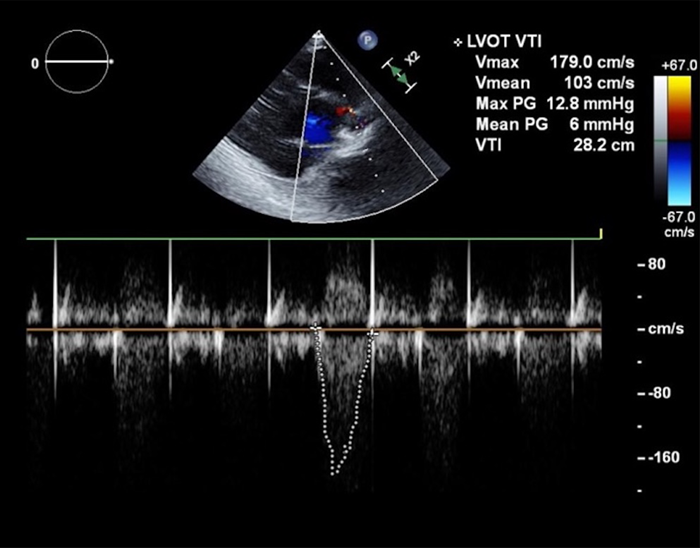

TTE

心尖部から中部にかけて前側壁で壁運動不良,中等度の大動脈弁逆流を認めた(Fig. 3).大動脈弁狭窄は評価困難であった.Simpson法にて左室駆出率40%,左室内径短縮率16%,拡張末期容積98 mL(76 mL/m2),収縮末期容積58 mL(45 mL/m2)と左心機能の低下を認めた.MRはわずかで,TRは中等度あり,三尖弁逆流圧較差は50 mmHgであった.両側の胸水もみられた.

Pediatric Cardiology and Cardiac Surgery 41(2): 91-96 (2025)

Fig. 3 Transthoracic echocardiogram on admission

The aortic regurgitation was mild, the aortic valve mean pressure gradient (mPG) was 6 mmHg, and the aortic valve maximal blood flow velocity (Vmax) was 1.79 m/sec.